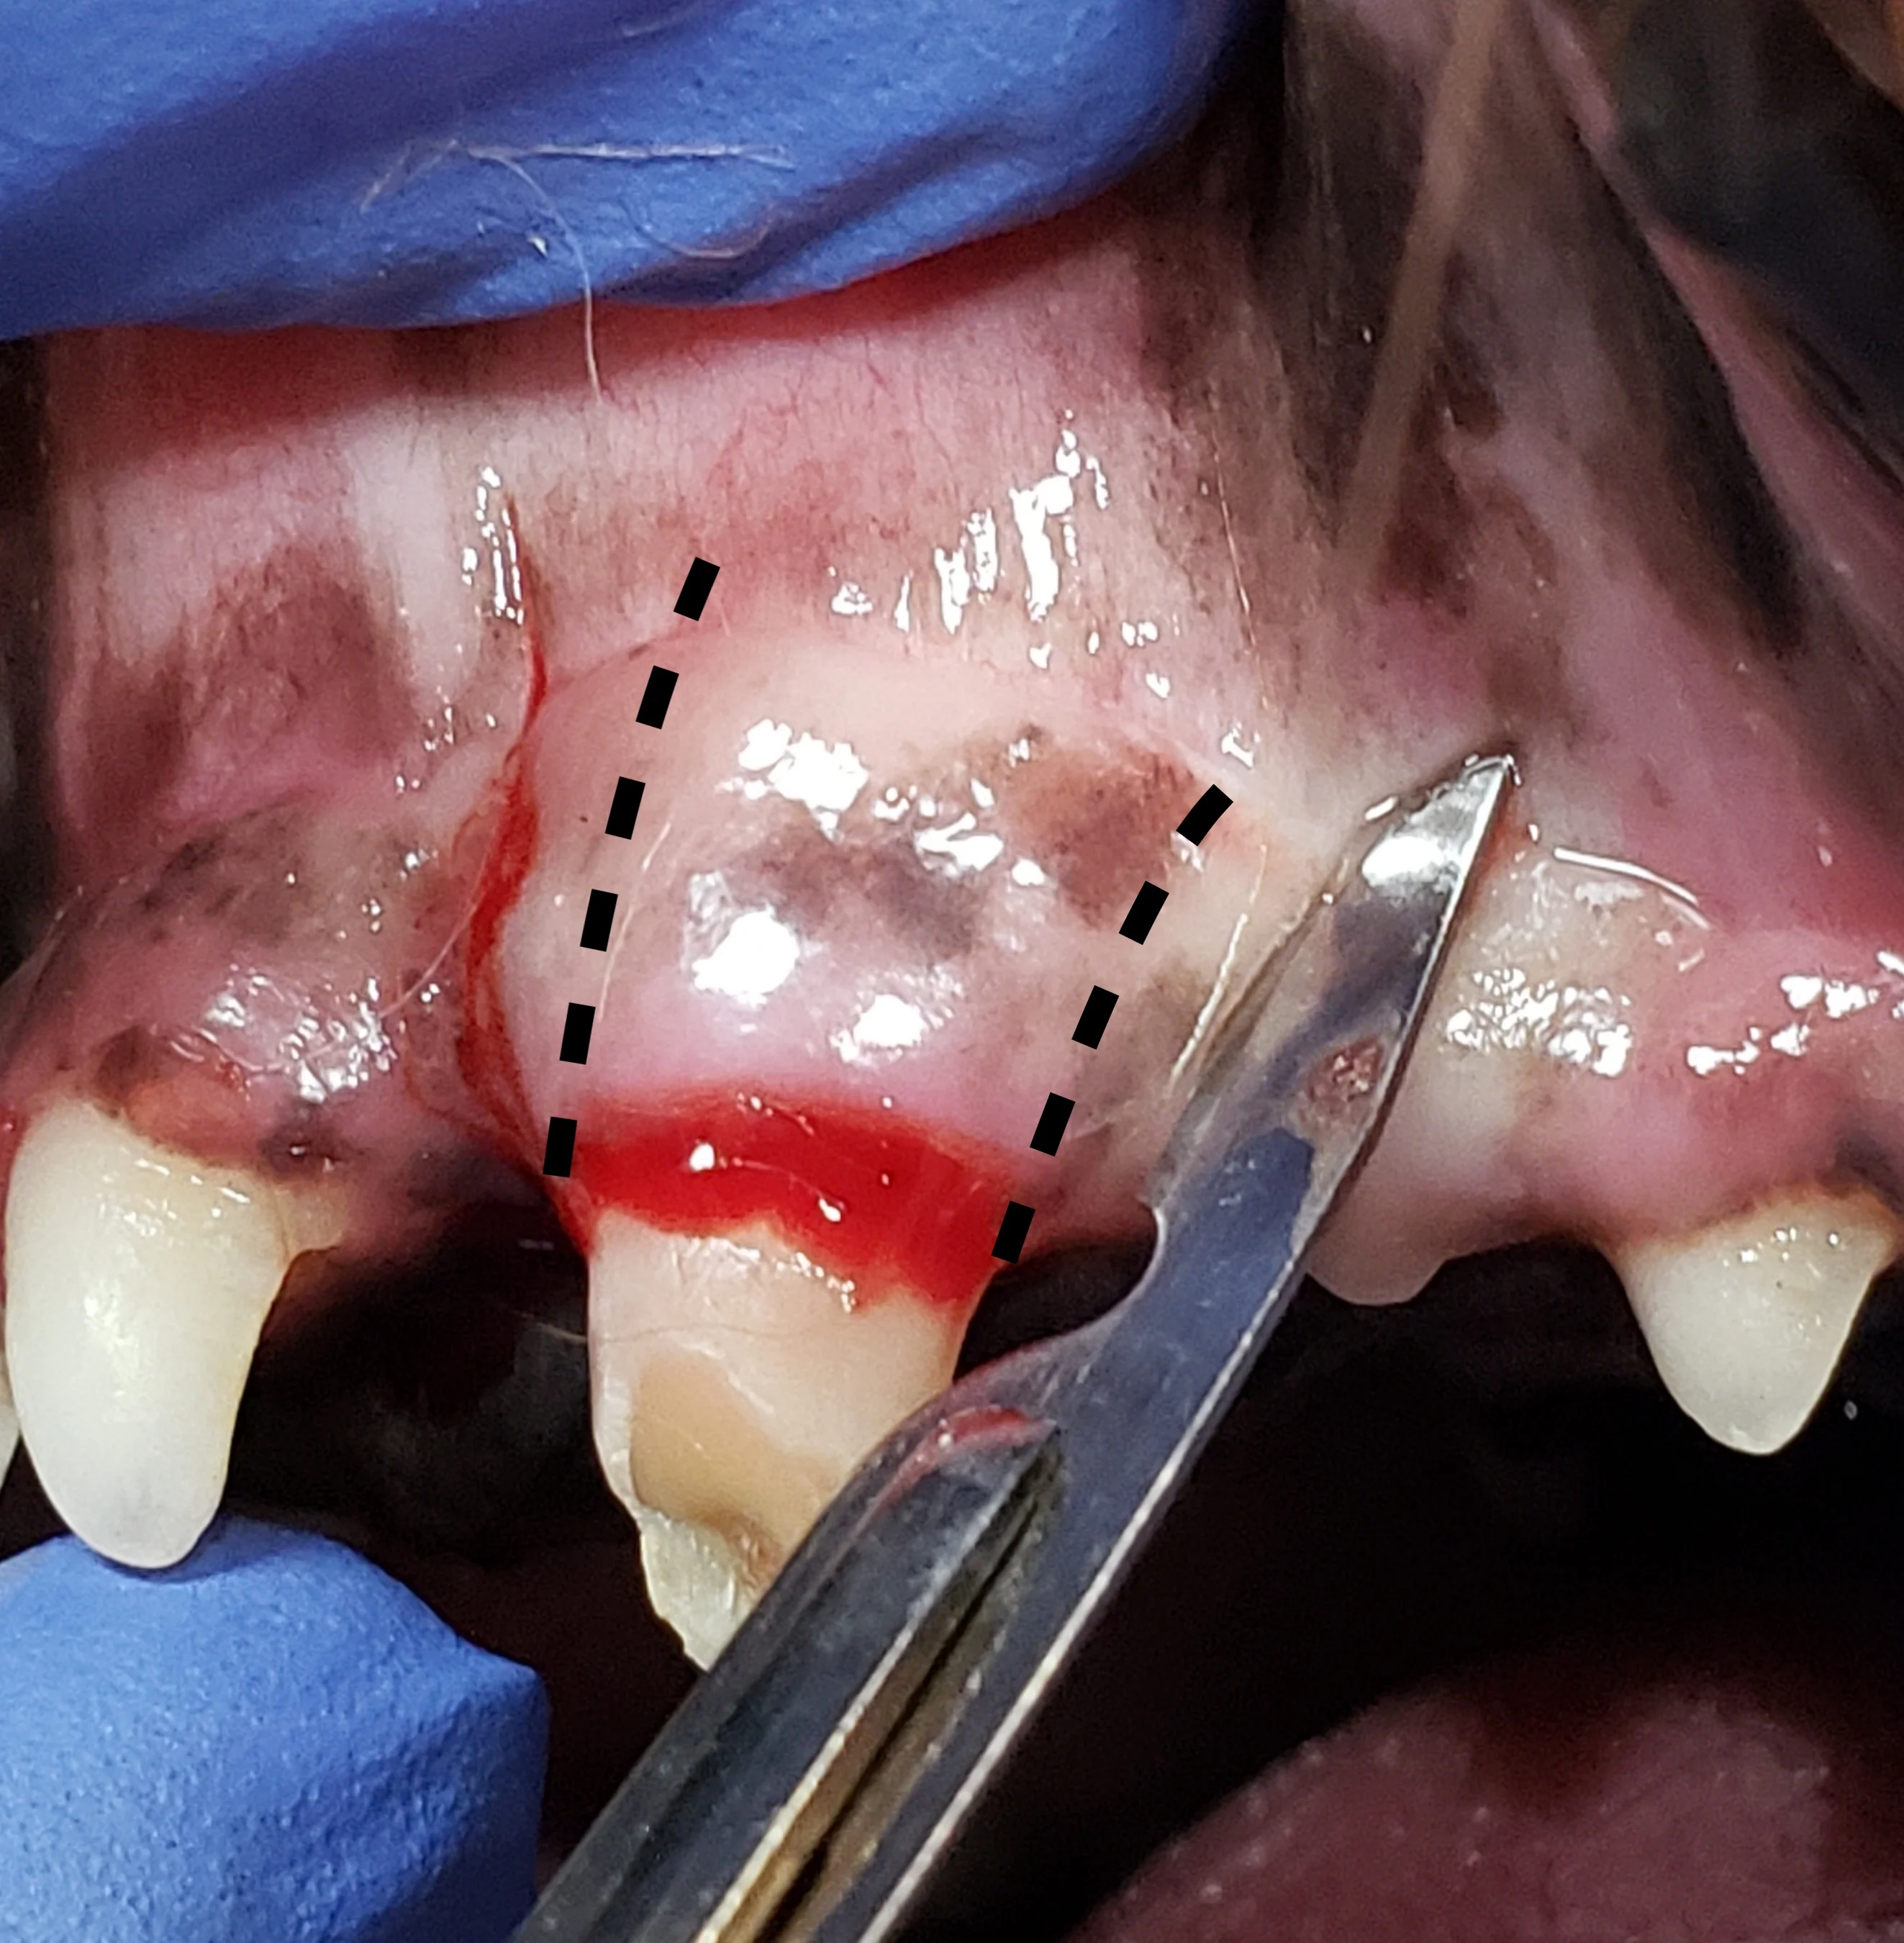

Step 2: Make Gingival Flap Releasing Incisions

Make releasing incisions for a full-thickness mucoperiosteal flap through the attached gingiva, past the mucogingival line, and at least a couple of millimeters into the alveolar mucosa to provide adequate exposure.

Rectangular Flap

A rectangular flap is created by making a mesial incision and a distal incision angled away from the tooth, following the distally curving position of the root. Releasing incisions should extend at least to the level of the widest part of the root and should be slightly divergent from each other, keeping the alveolar mucosa at the base of the flap wider than the coronal aspect with the attached gingiva, to provide enough tissue for closure. A flap wider at the gingival margin is important if an oronasal fistula is present. Making releasing incisions 1 to 2 mm from the outline of the tooth edge (dotted lines) places the incisions over bone, enhancing access to the periodontal ligament space and supporting the suture line following closure. In the author’s experience, this flap design provides optimal accessibility for tooth elevation and does not result in disruption of blood supply during healing.